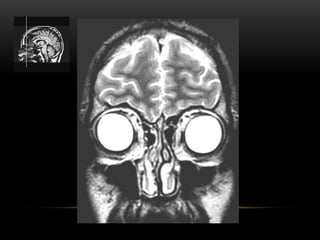

ANATOMIA TOPOGRÁFICA

Plano coronal

Giro frontal

superior

médio

inferior

Foice

inter-hemisférica

Seio sagital superior

Corpo caloso

(joelho)

Ventrículo lateral

(corno frontal)

Lobo

temporal